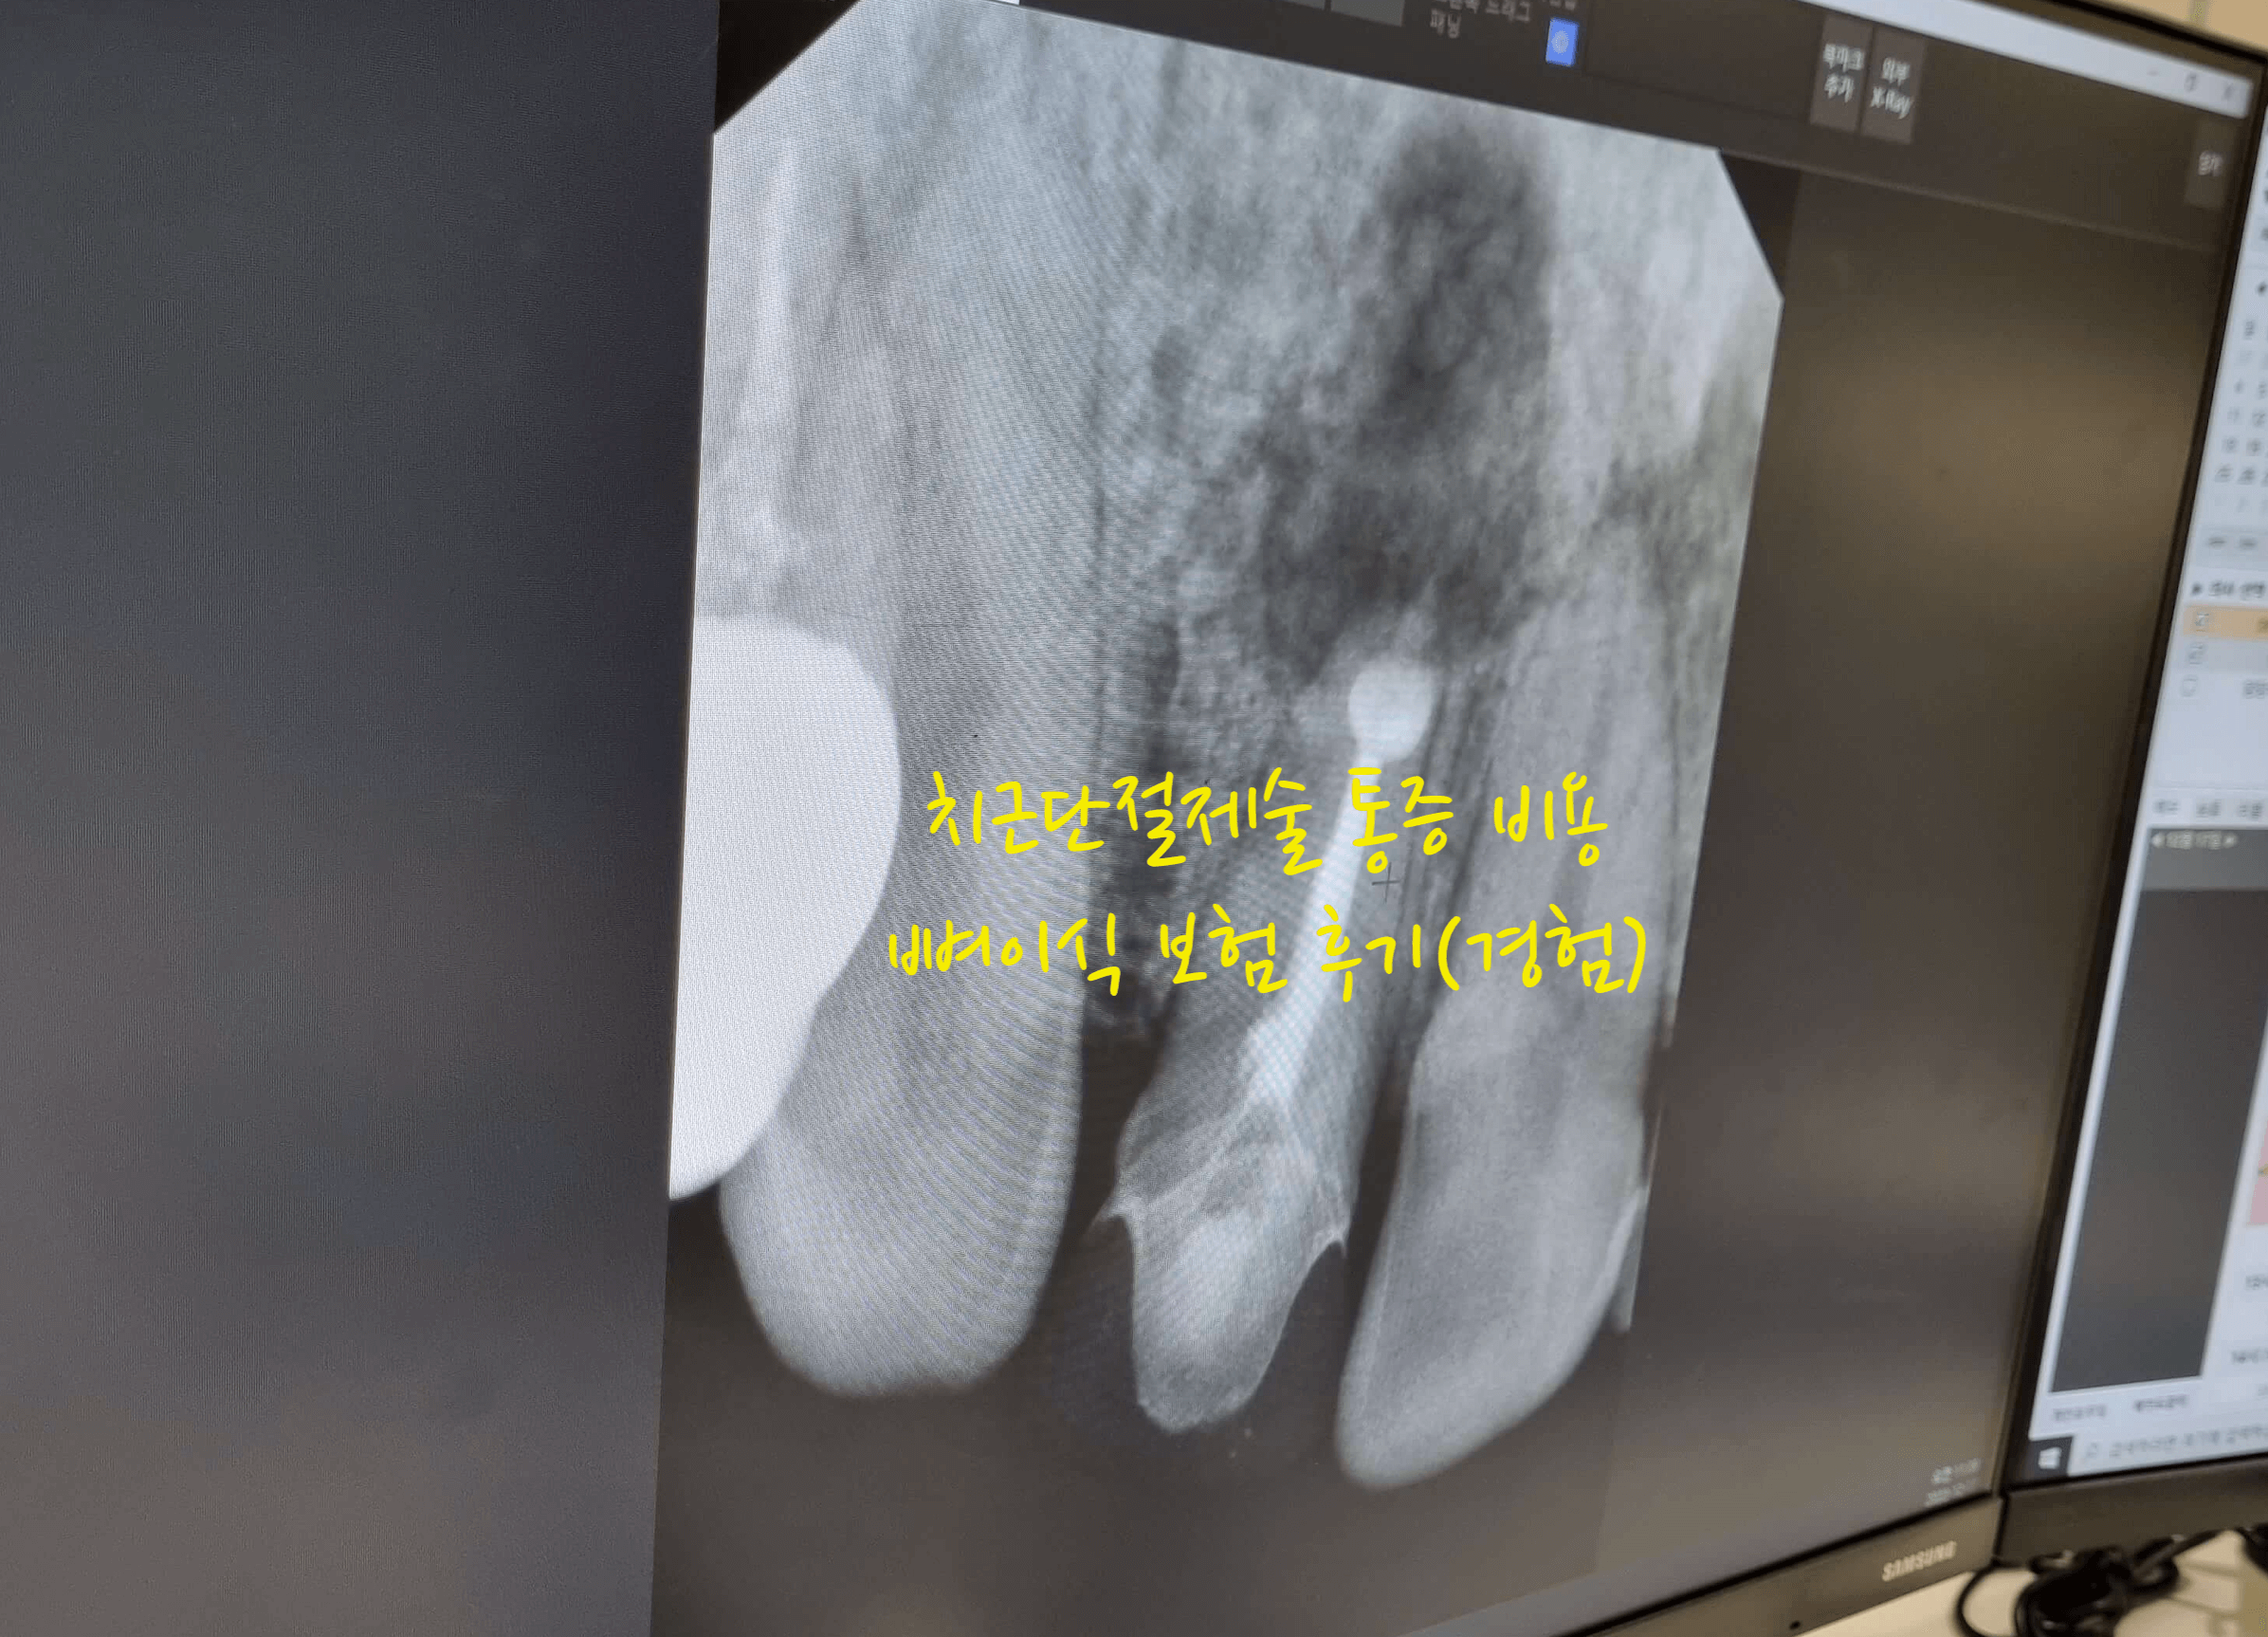

그러다가 시간이 흐르니 심한 통증을 느끼게 되고 또 하루 이틀지나면 괜찮아서 그냥 약먹고 지냈는데, 치과를 바꾼후 엑스레이를 찍었는데, 치과 의사선생님이 이거 이대로 방치하면 안되다고 염증이 뼈를 녹이고 있어서 치아를 뽑아 염증을 제거하던지 치근단 절제술을 해서 염증을 빼던지 해야 한다고 했습니다.

그렇게 오랜시간 치아뿌리에 염증을 방치 했더니 염증이 주변의 뼈를 녹여서 구멍이 나있는 수준이였습니다. 이렇게 염증을 계속 방치하는 경우 뼈를 녹이는 범위가 넓어져 전체적인 치아뼈대에 문제가 발생할수도 있기 때문에 염증이 있다면 바로 치료 및 조치를 받아야 합니다.